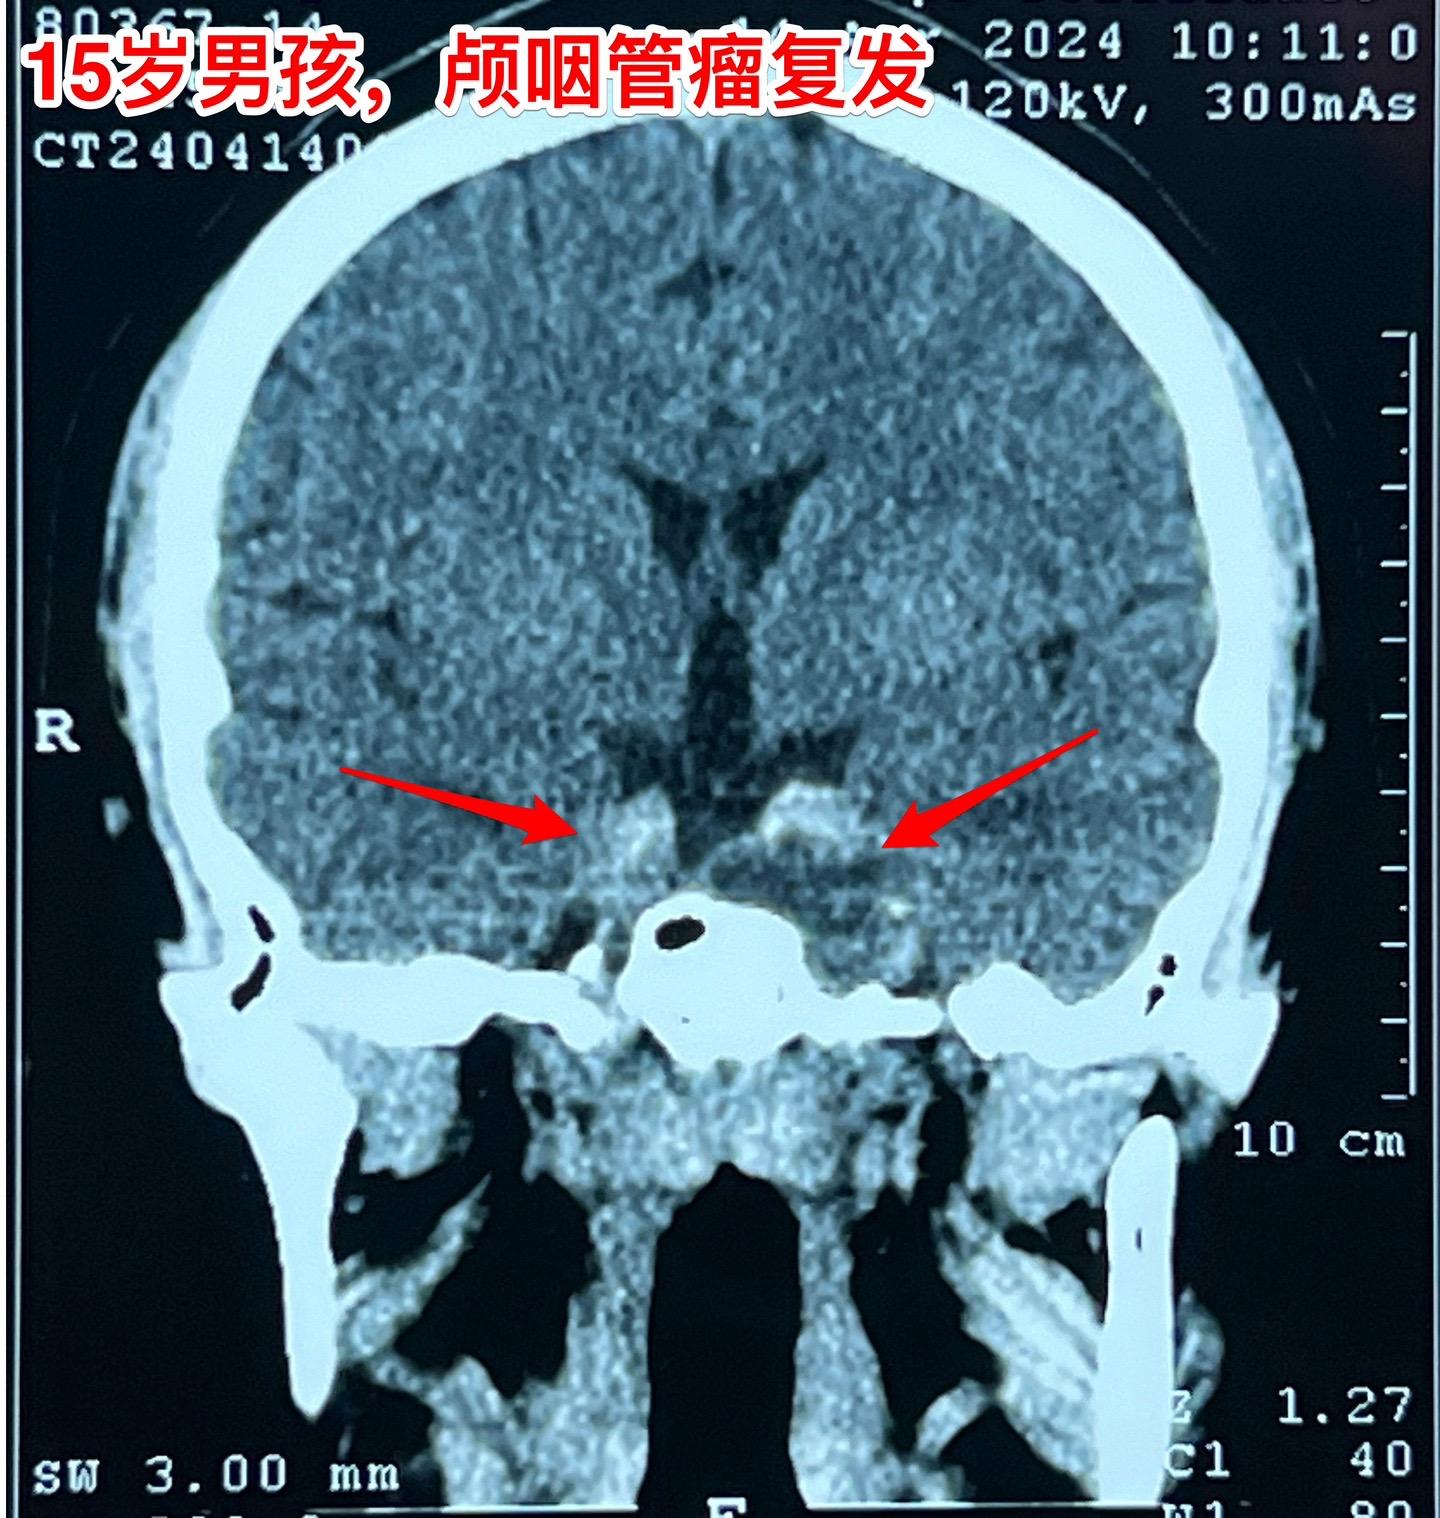

良性肿瘤也不一定容易治愈,颅咽管瘤就是。这个15岁大连市的男孩子因为颅咽管瘤先后作了两次手术,两次手术都是经鼻内镜手术。现在又复发了!从图片可以看见,这次肿瘤侵入左右两侧海绵窦,更难切除了。 在我科作了第三次手术,这次采用开颅手术。这样的手术医生很担忧出现脑脊液鼻漏的。这个病人手术后没有出现脑脊液鼻漏。 颅咽管瘤之所以容易复发是因为没有被彻底切除,如果彻底切除了也是可以治愈的。